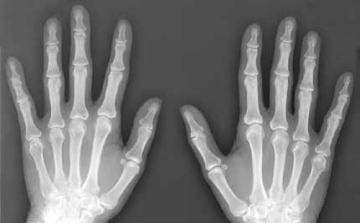

Kézközépcsonttörést szenvedett Nagy László, a Veszprém kézilabdázója

2018. Március 11. 09:51, vasárnap | Sport

Eltört a kézközépcsontja Nagy Lászlónak, a Telekom Veszprém kézilabdázójának.